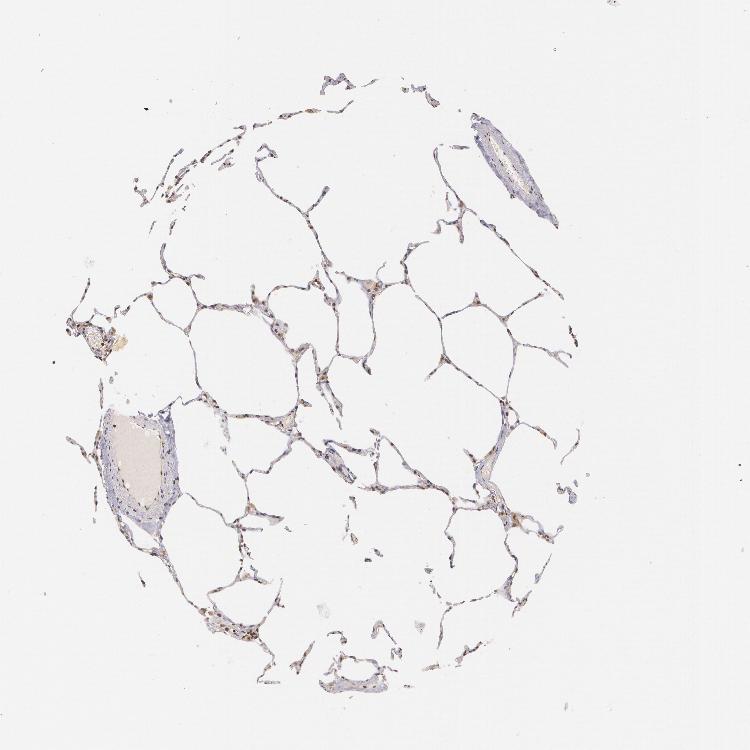

LUNG - Antibody stainingi

Antibody staining in the annotated cell types in the current human tissue is reported as not detected, low, medium, or high, based on conventional immunohistochemistry profiling in selected tissues. This score is based on the combination of the staining intensity and fraction of stained cells.

Each image is clickable and will lead to virtual microscopy that enables deeper exploration of all samples and also displays staining intensity scores, fraction scores and subcellular localization as well as patient and tissue information for each sample.

Antibody CAB002012

Alveolar cells Low

Macrophages Medium